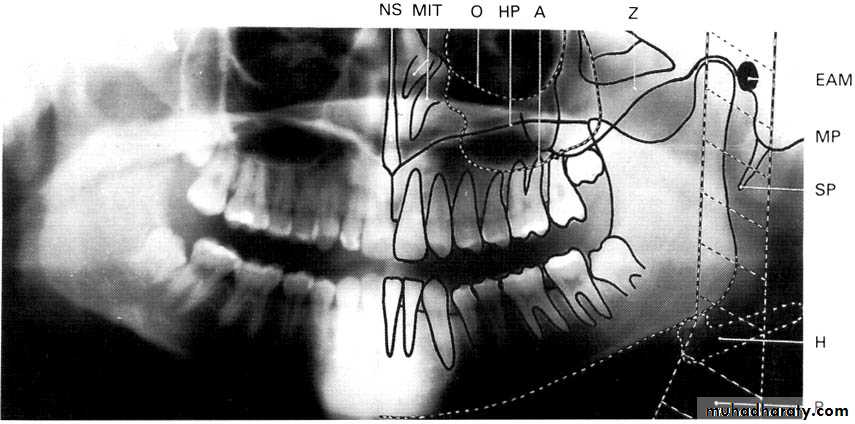

( hyoid bone, the hard palate, epiglottis).A dental panoramic tomograph showing the main real hard tissue shadows, including the plastic head support, drawn in on one side of the radiograph, NS — nasal septum,

MIT — middle and inferior turbinates, O — orbital margin, HP — hard palate, A — floor of antrum, Z — zygomatic arch, EAM — external auditory meatus, MP — mastoid process,

SP — styloid process, H — hyoid, P — plastic head support.